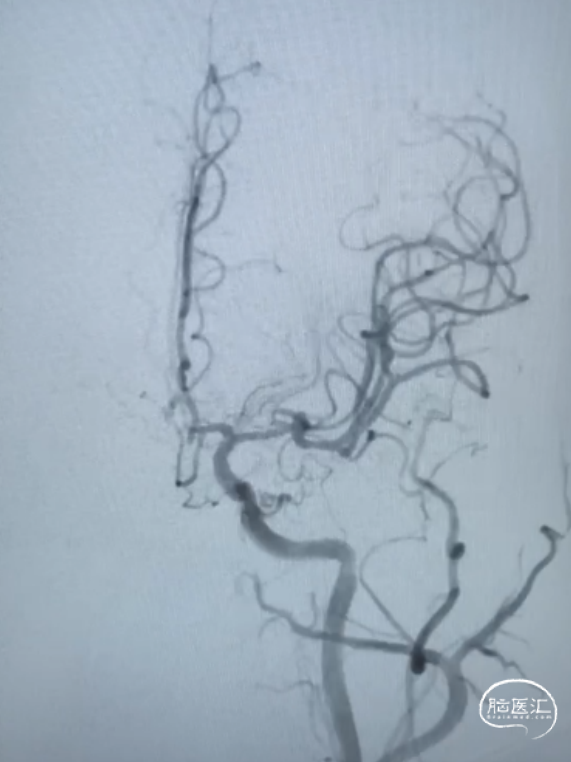

术前影像

患者取仰卧位,麻醉成功后,行双侧腹股沟处碘伏消毒3遍,铺无菌洞巾,以Seldinger法行右腹股沟股动脉穿刺,置6F动脉鞘,以5F多功能管造影可见左侧大脑中动脉M2段动脉瘤。